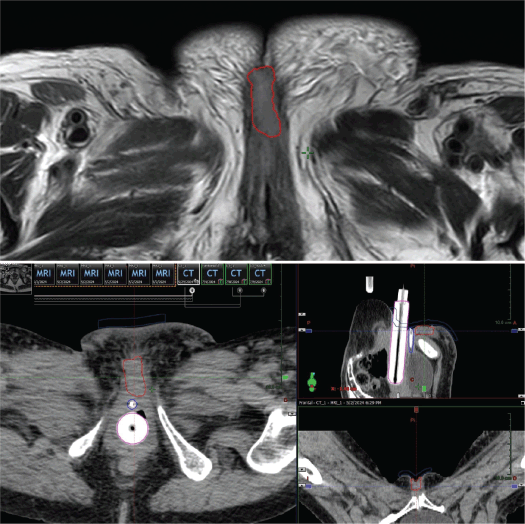

A key step was a detailed clinical exam to determine the extent of disease and the feasibility of placing interstitial catheters at a safe distance from the urethra. A planning CT (2.5 mm slices) was fused with a diagnostic MRI to precisely delineate the gross tumour volume (GTV) (Figure 1).

Figure 1. Case 1. Above, MRI of the pelvis, T2 sequence. The red line shows the GTV. Below, CT simulation for pre-plan design, on the axial, coronal and sagittal axis. The GTV is shown in red, the urethra in blue and the vaginal cylinder in pink.